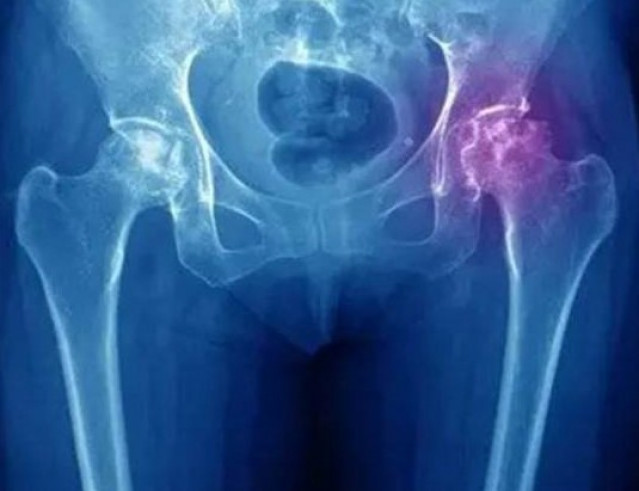

Асептический некроз тазобедренного сустава – это тяжелое заболевание, которое характеризуется нарушением кровообращения .....